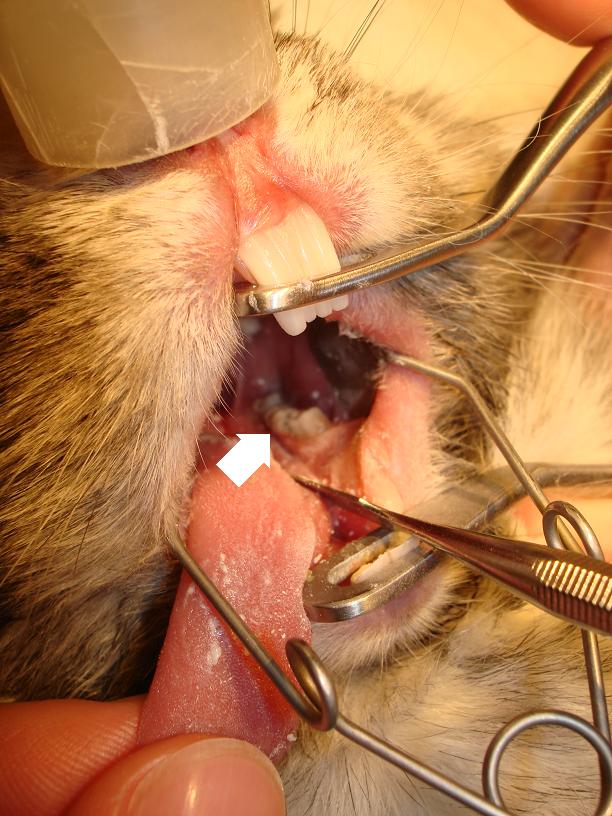

Na fotografiích můžete vidět přerůstání stoliček a formování zubů do špiček zraňujících sliznici jazyka:

Přerůstání zubů u králíků Přerůstání zubů u králíků